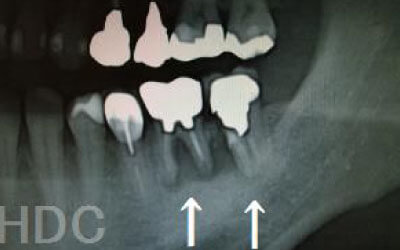

CTでは、骨や歯の状態を三次元で確認でき、正確な距離を測定することができます。

骨の厚さや傾き、神経の位置などを事前に詳しく計測することで、安全にインプラントを行うことができます。

2 神経を傷つけるリスク

インプラントの手術では、顎の骨を通る神経を傷つけるリスクがあります。

しかし、事前にCTでしっかりと撮影し、三次元的に神経との距離を計測して治療計画を立てることで、心配は不要です。

また、当院では削りすぎを防ぐためのストッパーも使用しています。